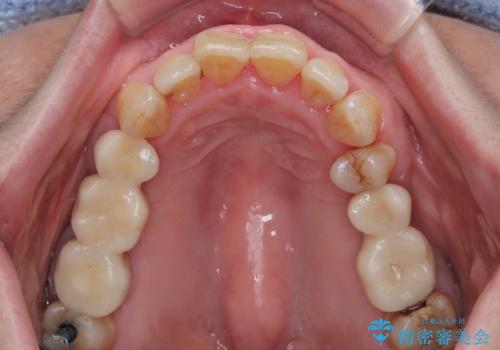

矯正治療を仕上げ、必要に応じて歯周外科処置を行い、適宜インプラントを埋入しながら咬み合わせを回復させていくこととしました。

最終的に奥歯はオールセラミッククラウンによる補綴治療を行うこととしました。

インプラントにより咬合が回復したことで、治療開始時に認められた上顎前歯の動揺も改善されました。